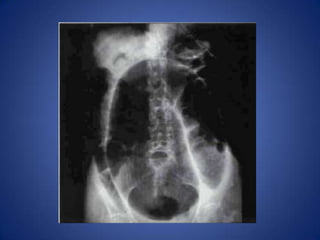

Sigmoid Volvulus

• Very elongated & dilated sigmoid colon,

folded back on itself ("coffee bean" or

"football" signs)

• Colon proximal to sigmoid will be dilated, but

not as much as sigmoid

• CT will show twisting of vessels in base of

sigmoid mesocolon

Sigmoid Volvulus • Veryelongated & dilated sigmoid colon, folded back on itself ("coffee bean" or "football" signs) • Colon proximal to sigmoid will be dilated, but not as much as sigmoid • CT will show twisting of vessels in base of sigmoid mesocolon